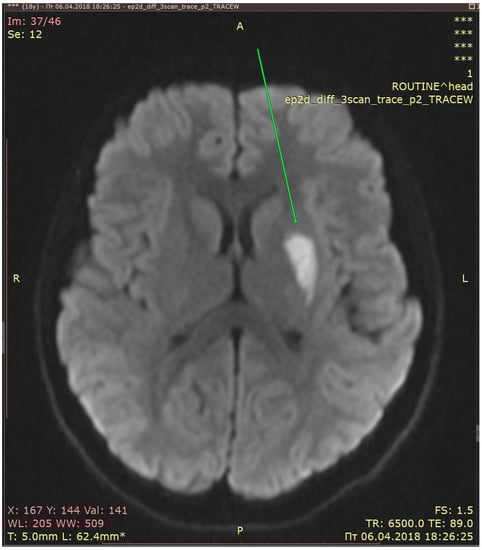

2.3. Diagnostic Assessment and Evaluation